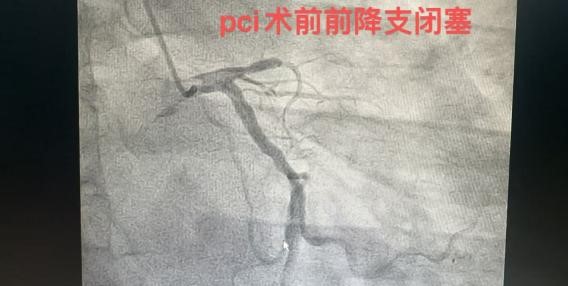

“急诊!急诊!急诊!”微信工作群里,急促的铃声打破了寂静的深夜,是胸痛中心发来的消息,有人突发急性心梗,需要马上进行急诊介入治疗!菏泽市创伤医院(市六院)心血管介入科主任张吉宏一声令下,心血管介入团队成员十分钟之内全部到岗,开始争分夺秒抢救患者生命!

“顺利开通,三级血流恢复!”张吉宏主任脱下沉重的铅衣,用手机在微信群里回复着,汗水早已浸透了他的工作服,来不及收拾,他又忙着和患者家属去讲解手术过程了....

中秋国庆双节期间,菏泽市创伤医院(市六院)心血管介入团队,在完成多台日间手术的同时,同时顺利完成多台急诊PCI手术,挽救了一个又一个的生命和家庭。